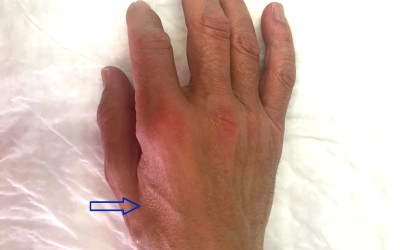

Thumb base osteoarthritis: first carpometacarpal osteoarthritis

Created:20-10-2012 || Updated: 10-02-2020